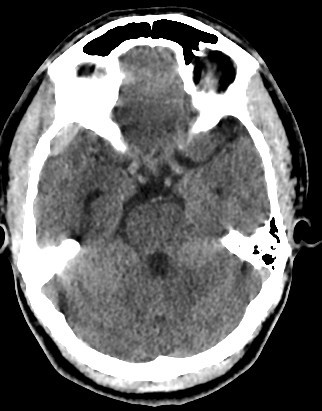

brain CT scan

brain CT scan History

A brain CT scan, also known as a computed tomography scan or CAT scan, is a non-invasive imaging procedure that uses X-rays to create detailed cross-sectional images of the brain and surrounding structures. It's a common diagnostic tool for evaluating head injuries, strokes, brain tumors, and other neurological conditions. Here's a more detailed explanation: What it is: A brain CT scan uses a series of X-ray beams that rotate around the head, capturing multiple images from different angles. These images are then processed by a computer to create detailed cross-sectional views of the brain, allowing doctors to visualize the brain's structures and identify any abnormalities. The scan can be performed with or without contrast dye, which helps to highlight certain tissues and blood vessels for better visualization. Why it's used: Traumatic brain injuries: CT scans are often the first imaging test used to assess the extent of head injuries and identify potential fractures, bleeding, or swelling. Stroke: CT scans can quickly identify whether a stroke is caused by a blood clot (ischemic stroke) or bleeding (hemorrhagic stroke), guiding appropriate treatment. Brain tumors: CT scans can help detect and assess the size and location of brain tumors. Other neurological conditions: CT scans can also be used to diagnose conditions like hydrocephalus (excess fluid in the brain), aneurysms (bulges in blood vessels), and certain types of dementia. Guiding procedures: CT scans can be used to guide biopsies or other procedures involving the brain. What to expect during the procedure: You will lie on a table that slides into the CT scanner, which is a large, doughnut-shaped machine. The scan itself is painless, but some people may experience slight discomfort from lying still on the hard table. If contrast is used, you may feel a warm or flushing sensation, or a metallic taste in your mouth. The scan typically takes only a few minutes. Risks and Precautions: CT scans involve exposure to radiation, but the risk from a single scan is generally considered low. If you are pregnant, it's important to inform your doctor, as alternative imaging methods may be considered to avoid exposing the fetus to radiation. If you have any allergies, particularly to contrast dye, make sure to inform your doctor.